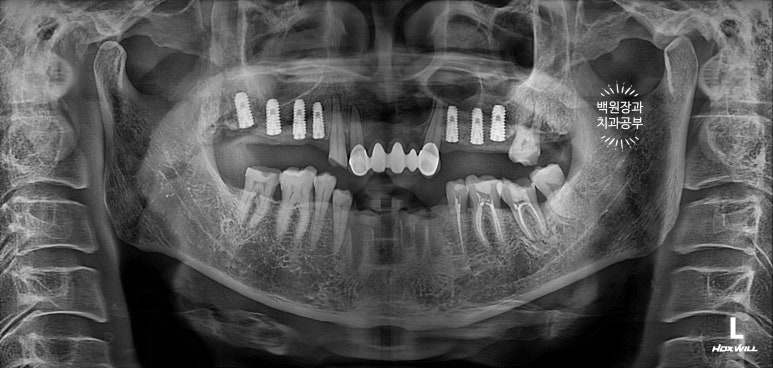

치과용 파노라마 엑스레이를 보시면 더 드라마틱한 변화를 느끼실 수 있어요.

다수의 치아가 씌워지고, 임플란트로 회복되어 마치 사이보그같은(?!) 느낌이 들긴 하지만,

정갈하게 치료가 잘 된 느낌입니다.!!!

임플란트의 위치가 적절히 배치되어 있어, 임플란트에서 크라운까지 이어지는 emergency profile이 예술이네요.

들쭉날쭉한 치아 없이 조화로운 교합이 형성되어 있는 것을 보실 수 있을거에요.

교합평면도 가지런하게 형성되어 보입니다.